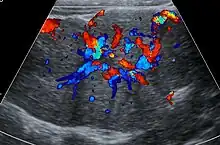

Lorsqu’elle est visible, la cicatrice centrale est hyperéchogène[1],[3],[12] (mais possiblement hypoéchogène [6]). L’étude en Doppler couleur permet de visualiser au centre de la lésion une hypervascularisation traduisant la présence de l’artère afférente[12].

L’étude en Doppler pulsé met en évidence des vitesses systoliques élevées[6],[12] et un index de résistance d’environ 0,5[1],[3].